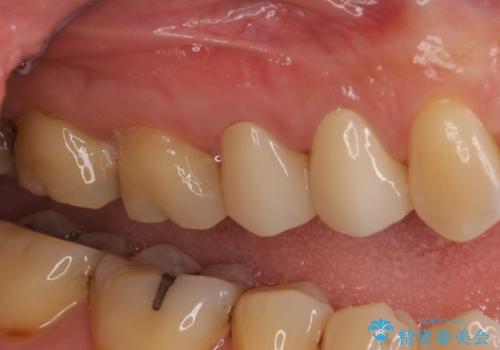

今回はまず欠けた場所を修復して見た目を回復させたのち、ラミネートべニアの仮歯をつくり、しばらく使用して考えて頂きました。メリットやデメリットを説明した結果、外れにくいセラミッククラウンをご選択頂きました。

咬み合わせや元のご自身の歯の色に特徴があったため、セラミッククラウンを修正したり、隣の歯を金属を外して白いつめものに変えたりして経過観察を長めに行いました。

患者様には大変満足して頂きました。